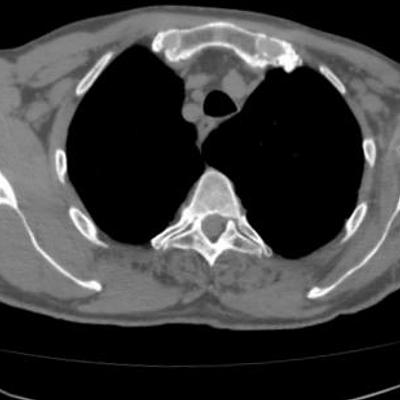

Orthopaedic workflow for hip prosthesis replacement: A 3D CT-scan (a) is segmented into labels (b). This discrete volume image is converted to a volume mesh (c). Based on medical simulations (d) [1], optimal implant design and positioning can be determined.